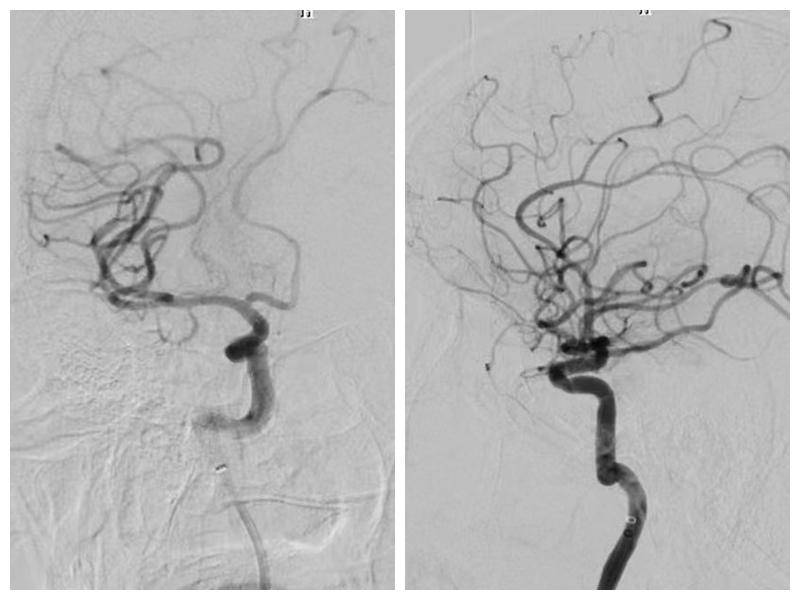

在神经内科刘勇副主任和吴继华主治医师的共同协作下,共进行4次支架取栓,18:50,经中间导管造影见闭塞血管前向血流恢复,血管达到mTICI3级再通,手术顺利完成。

术后造影